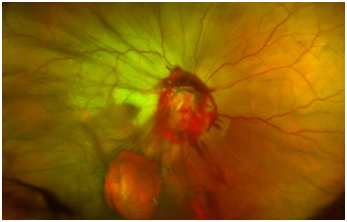

A 15-year-old healthy male presented with an ocular injury sustained while playing basketball. He described a finger poke incident with the contact made with the lower aspect of his right eye. Immediately following the injury, he described loss of vision of the right eye. On presentation to the emergency eye clinic 2 hours later, his visual acuity was no light perception in the right eye. A right relative afferent pupillary defect was present. A conjunctival tear and associated chemosis was present in the inferior bulbar conjunctiva. A micro-hyphaema with 2+ red cells was found in the anterior chamber but the cornea, lens and intraocular pressure were all normal. Examination of the posterior segment revealed localized vitreous haemorrhage arising from the disc. The disc itself appeared disorganized and recessed behind the globe with an obvious defect in the disc superiorly (Figure 1). Gentle palpation of the globe during fundus examination showed that some streaks of vitreous haemorrhage adjacent to the disc were mobile and could pass through the disc defect with gentle palpation and return into view on release of palpation. There was retinal pallor affecting the superior temporal and nasal aspects of the retina (Figure 2). A B-Scan ultrasound demonstrated alteration in the normal contour of the optic nerve/ globe junction and hypo echogenic area adjacent to the nerve (Figure 3). MRI of the brain and orbit showed disruption in the area of lamina cribrosa of the right eye (Figure 4). At 3 weeks following the injury, progressive dense vitreous haemorrhage prevented visualization of the posterior pole (Figure 5). Subsequent follow up after one month showed that the vitreous haemorhage disperse spontaneously, with persistent optic nerve disorganization and no improvement in vision.

Figure 2 Wide field fundus image demonstrating superior retinal pallor secondary to optic nerve pallor.